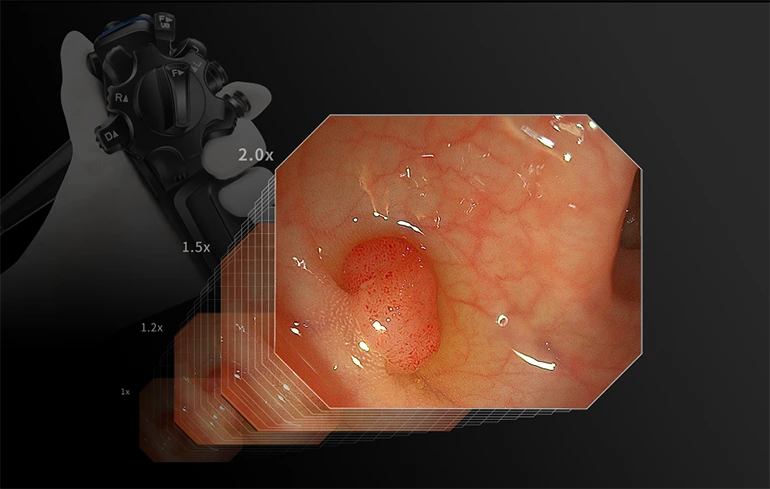

Обработка изображений

Увеличение деталей

Опция четырехуровневого увеличения

Акцентирование структур

Добавьте выразительности структурной форме изображения

Акцентирование контуров

Добавьте четкости краям и контурам